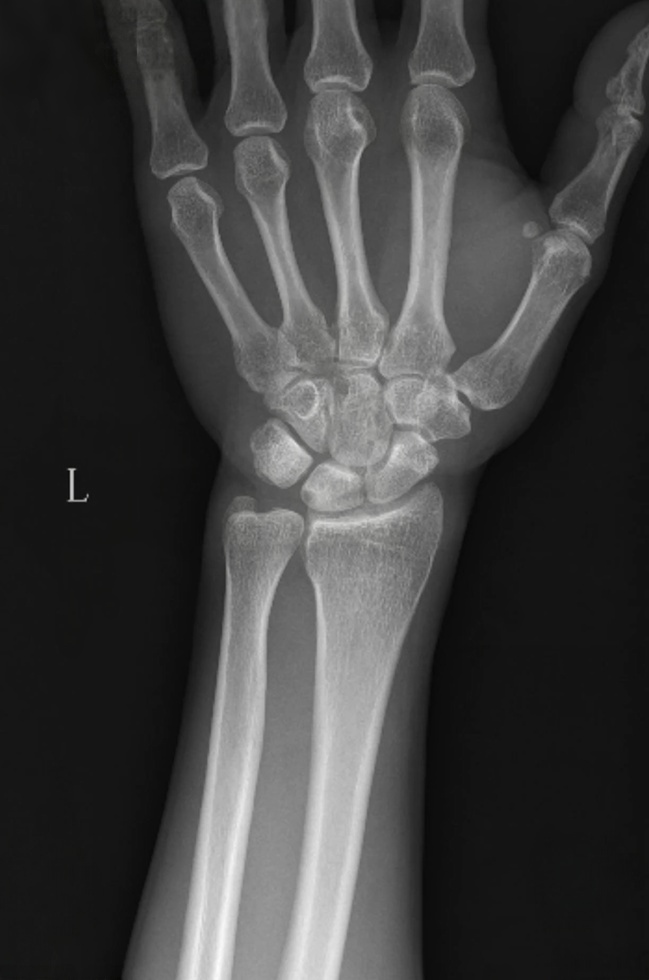

X线片示:尺骨正向变异,月骨可见低密度囊性透亮影。